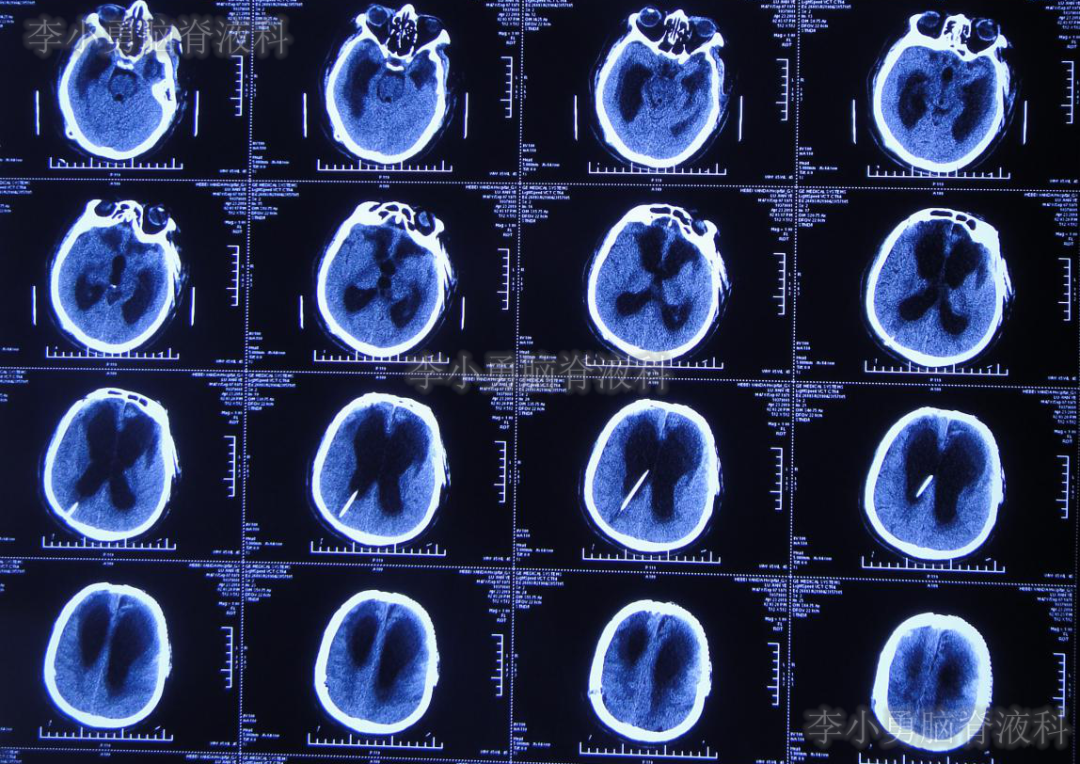

颅骨修补术+脑室腹腔分流术后105天即2019年7月12日(脑外伤术后194天),转至李小勇脑脊液科。入院时:患者呈昏迷状态,体温高,留置胃管、气管切开套管(图-9)。入院当天行头颅CT(图-10)示脑室扩张、腹部CT检查(图-11)可见肝区巨大的囊肿,其内可见引流管,考虑囊肿内为脑脊液。

图-10:2019年7月12日入院时头颅CT

由于患者脑室明显扩大,且肝区巨大水囊(引流管包裹形成),考虑分流管已发生堵塞,故入院当天紧急行脑室外引流术+原分流管拔除术。术后次日复查头颅CT(图-12)示引流管位置良好,无出血。

图-12:2019年7月13日头颅CT

术中留取的脑脊液标本培养5天后回报为表皮葡萄球菌,给予抗感染治疗。经过20天的治疗,患者脑脊液中细菌消失,且发热症状消失。于2019年8月6日常规复查头颅CT(图-15)示脑室略缩小,当日改行脑室长程引流术。

图-15:2019年8月6日头颅CT术前复查

术后常规复查头颅CT(图-16)示引流管位置良好。

图-16:2019年8月6日头颅CT术后复查